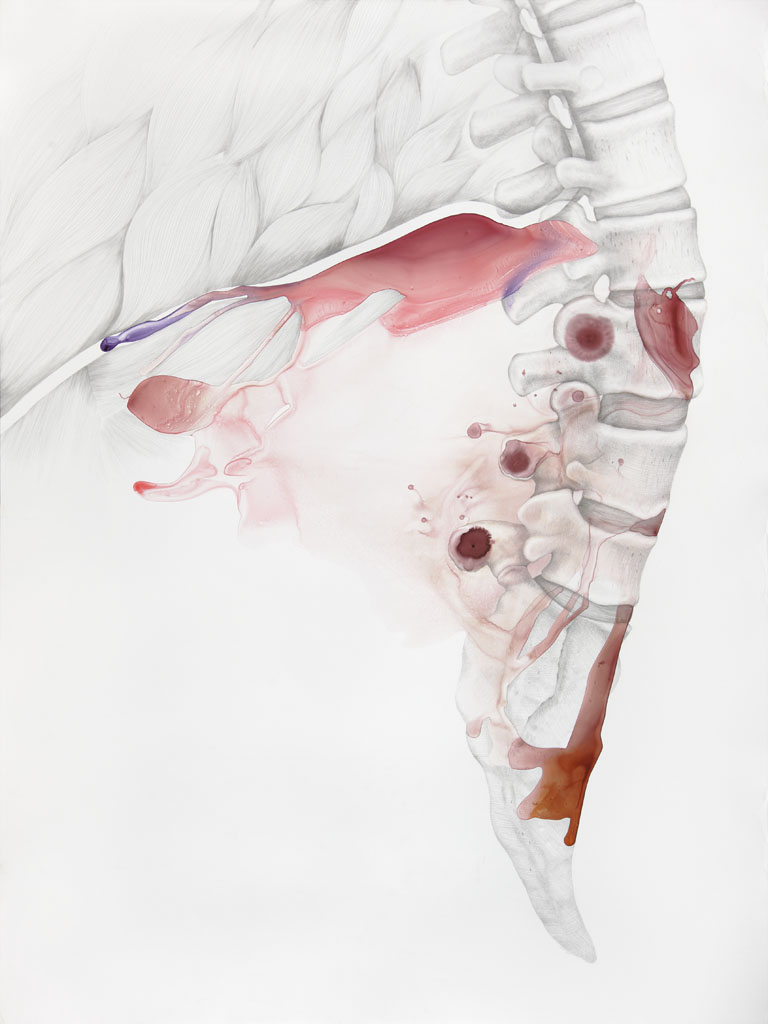

While working on several projects and experimenting with various media, somewhere along the way I developed an interest in medical illustration as a visual representation of the human body. I began reading philosophy texts on the human body and how we define it. I am very much interested in the fact that a medical illustration can never be an objective representation of the body. We all have subjective visceral experiences that differ from person to person, and these cannot be visually represented without something being lost in translation.

Ever since I became interested in this topic, I’ve been creating drawings and paintings that mix technical scientific images with things that are generally not meant to be there: abstract inkblots, random humorous intrusions and additions, sudden changes in rendering… The work tries to hint at things that medical illustration cannot represent—things that are very much embodied. Human experiences of pain, love, confusion, fear, happiness—all of these kinds of things reside in the body.

Photos of my work are available on my website but seeing those is not the same as seeing the work itself. Some of my drawings and paintings are several feet tall with unusual surfaces and textures that require movement while viewing. Regarding supporting my work, all of my paintings are for sale. If you are in the Chicago area and might be interested in purchasing a piece, you are welcome to come for a studio visit.